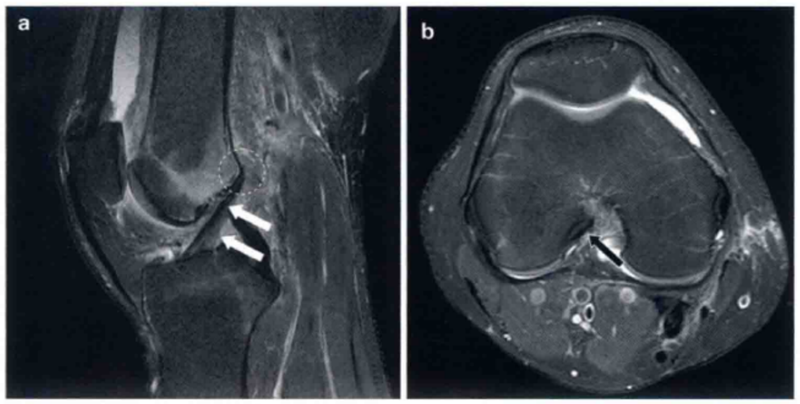

图4 a和b显示的为类似ACL损伤的表现。

a显示ACL完整,轻度松散黏液状降解(箭头)。a中ACL为增强的T2高信号,但是走行是正常的,没有不连续的病变,股骨附着点完整。b显示了完整的ACL和ACL腱鞘囊肿(箭头)